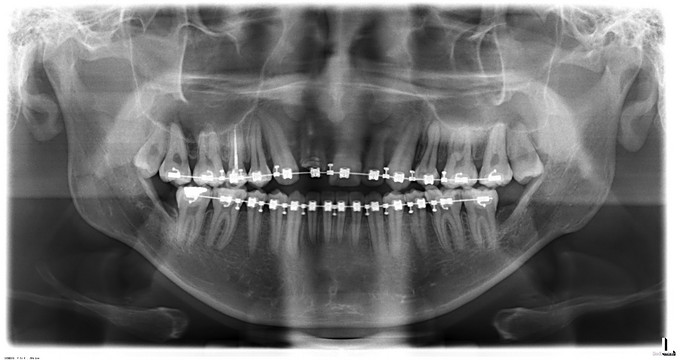

诊断:1.上颌后缩2.下颌前突,全麻下行上颌LeFortⅠ型截骨前徙术+双侧上颌骨骨内坚固内固定术+双侧下颌骨矢状劈开后退术+去骨皮质术+坚固内固定术+双侧邻近瓣转移修复术。

现患者生命体征平稳,一般情况可,双侧面部轻度肿胀,口内创口缝线固定在位,负压引流管已拔出,咬合可。请示上级医师,同意今日出院